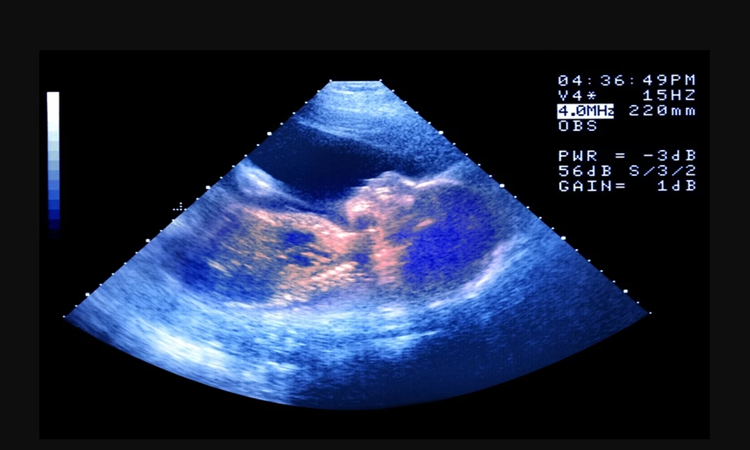

No dia 26 de julho nasceu em Ohio, nos Estados Unidos, Thaddeus Daniel Pierce, bebê gerado a partir de um embrião congelado em 1994. O intervalo de mais de três décadas entre a fertilização e o nascimento garantiu o recorde mundial de embrião humano mais antigo a resultar em parto bem-sucedido,

O embrião foi originalmente criado nos anos 1990 para Linda Archerd, à época com quatro embriões resultantes de tratamento de fertilização in vitro (FIV). Um deles levou ao nascimento de uma menina, hoje com 30 anos, e os outros três foram criopreservados.